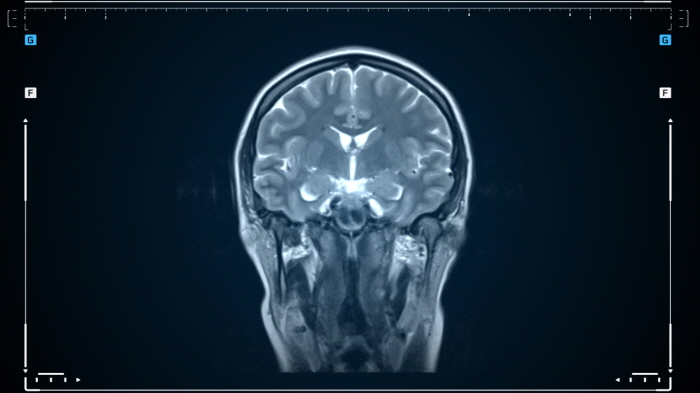

이 질환은 발작, 두통, 인지 기능 저하, 뇌수종 등 다양한 증상을 유발하며, 진단을 위해 MRI, CT 촬영 및 혈액 검사가 필요합니다.

ㆍ MRI(자기공명영상): 뇌 속 유충의 위치와 크기를 정확히 확인할 수 있습니다.

ㆍ CT(컴퓨터 단층촬영): 유충에 의해 뇌에 생긴 병변을 확인합니다.